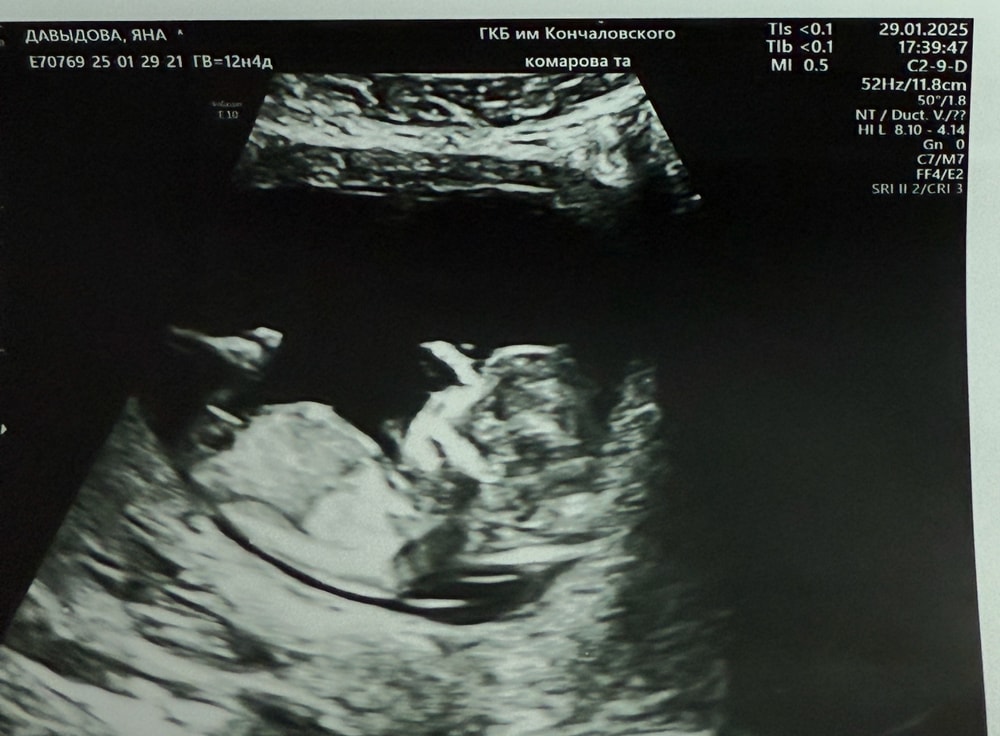

Скрининг, как думаете кто мальчик или девочка

Девочки, всем привет) кто в этом разбирается, напишите пожалуйста, видно ли кто у нас мальчик или девочка?